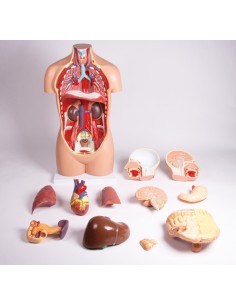

3B Scientific, Torse bisexuel, modèle de luxe, séparable en 20 parties B32

3B Scientific, Torse bisexuel, modèle de luxe, séparable en 20 parties B32

3B Scientifique, torse bisexuel japonais, décomposable en 18 parties B32/4

3B Torse scientifique, africain bisexuel, décomposable en 24 parties B37

3B Scientific, mini torse humain sans tête, décomposable en 9 parties B20

Du crâne en 22 parties à verrouillage magnétique aux modèles de colonne vertébrale, des modèles d'articulation aux modèles de cœur, chaque pièce de notre collection est conçue pour une immersion totale dans l'étude de l'anatomie humaine. Nos modèles, réalisés à partir de scans d'os réels, garantissent une expérience tactile authentique et une fidélité de poids presque identique aux originaux.

Indispensables aux étudiants comme aux professionnels, nos modèles anatomiques sont des outils pédagogiques qui permettent d'observer les structures anatomiques avec précision, en évitant les dissections ou les études invasives. Ils sont également utiles pour expliquer les pathologies aux patients, ce qui rend la communication plus efficace et permet de gagner un temps précieux.